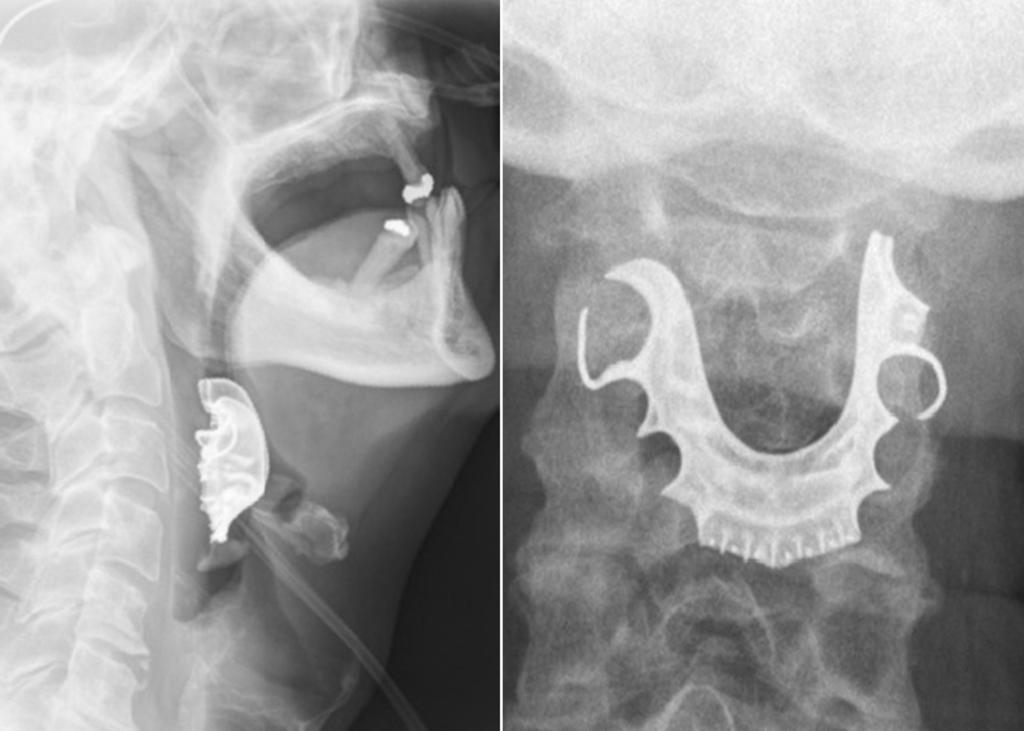

Dos días más tarde el hombre regresó al hospital, pues sus síntomas habían empeorado. Le revisaron la garganta y descubrieron el objeto extraño. Una radiografía después, se dieron cuenta de que era una dentadura postiza alojada en la garganta.

El hombre dijo que había perdido la prótesis después de la cirugía, lo que indica que se la tragó luego de ser anestesiado. Se le sometió a otra cirugía, para extraer el objeto, y una semana después fue dado de alta.